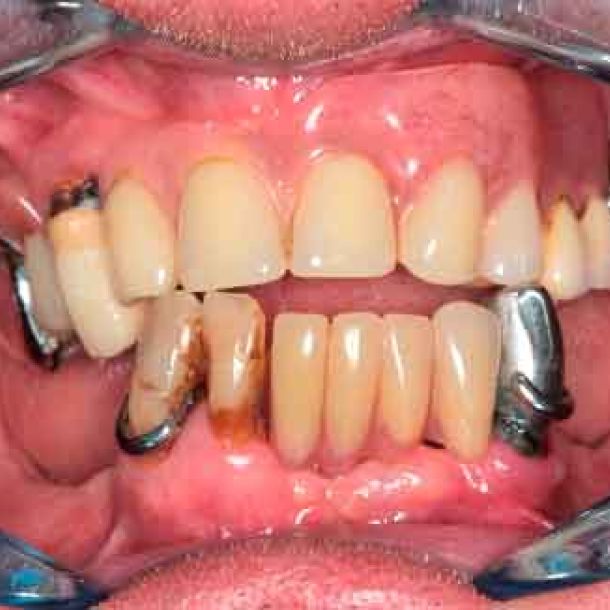

Patient de 66 ans. Souhaite retrouver un confort fonctionnel et améliorer l'esthétique.

Plaintes

- Manque de stabilité de ses prothèses amovibles

- Difficultés à manger

- Affaissement de la lèvre supérieure

Les structures parodontales des dents restantes ne sont plus suffisantes. Une édentation est envisagée. Le plan de traitement est orienté vers une prothèse complète maxillaire amovible et une prothèse complète mandibulaire supportée par des implants. Le défi est de passer de la situation initiale aux provisoires en utilisant les données du patient.